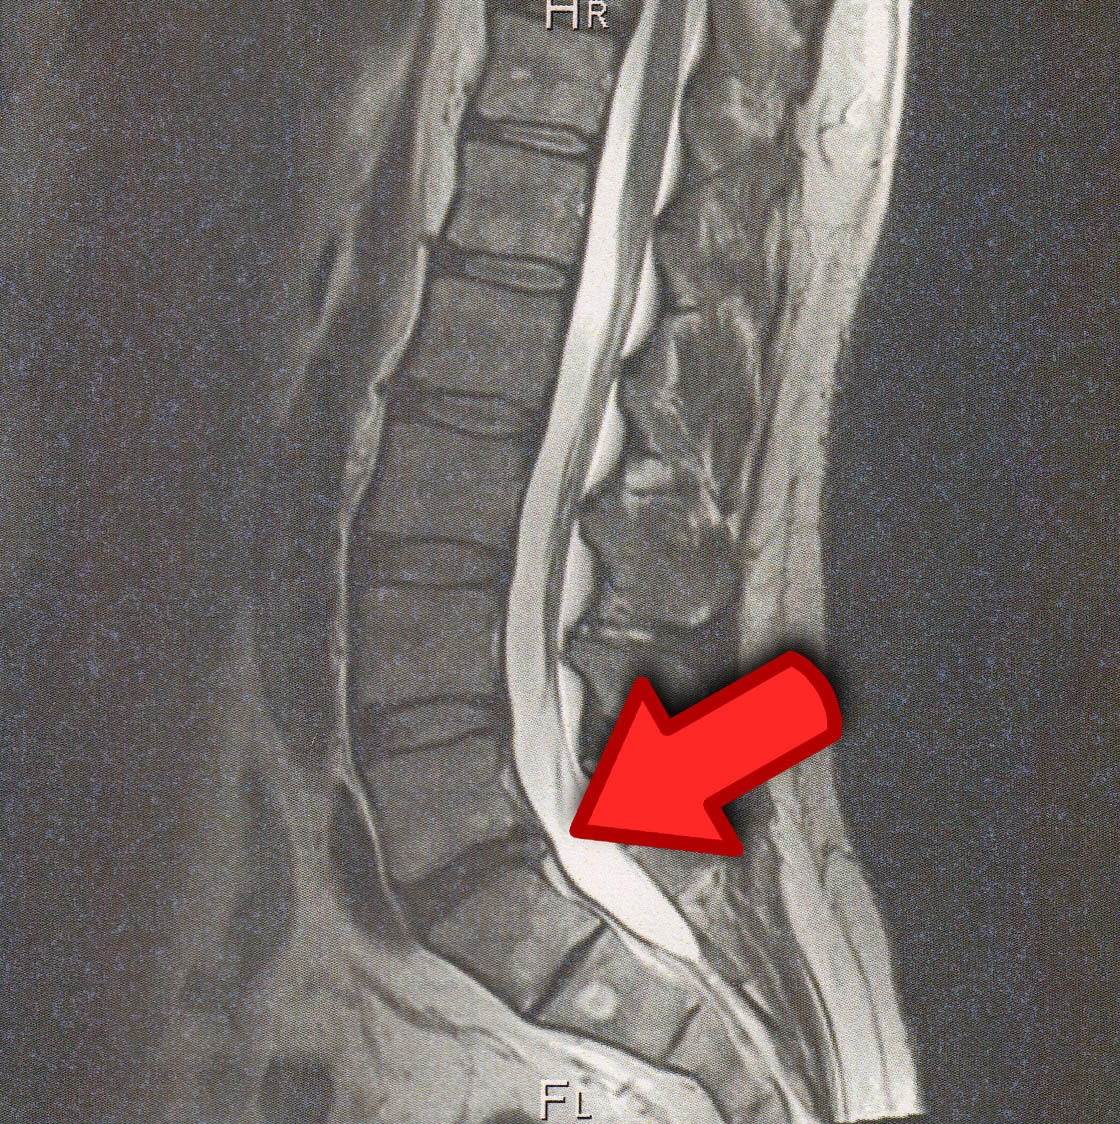

Диски L5 S1 Фото